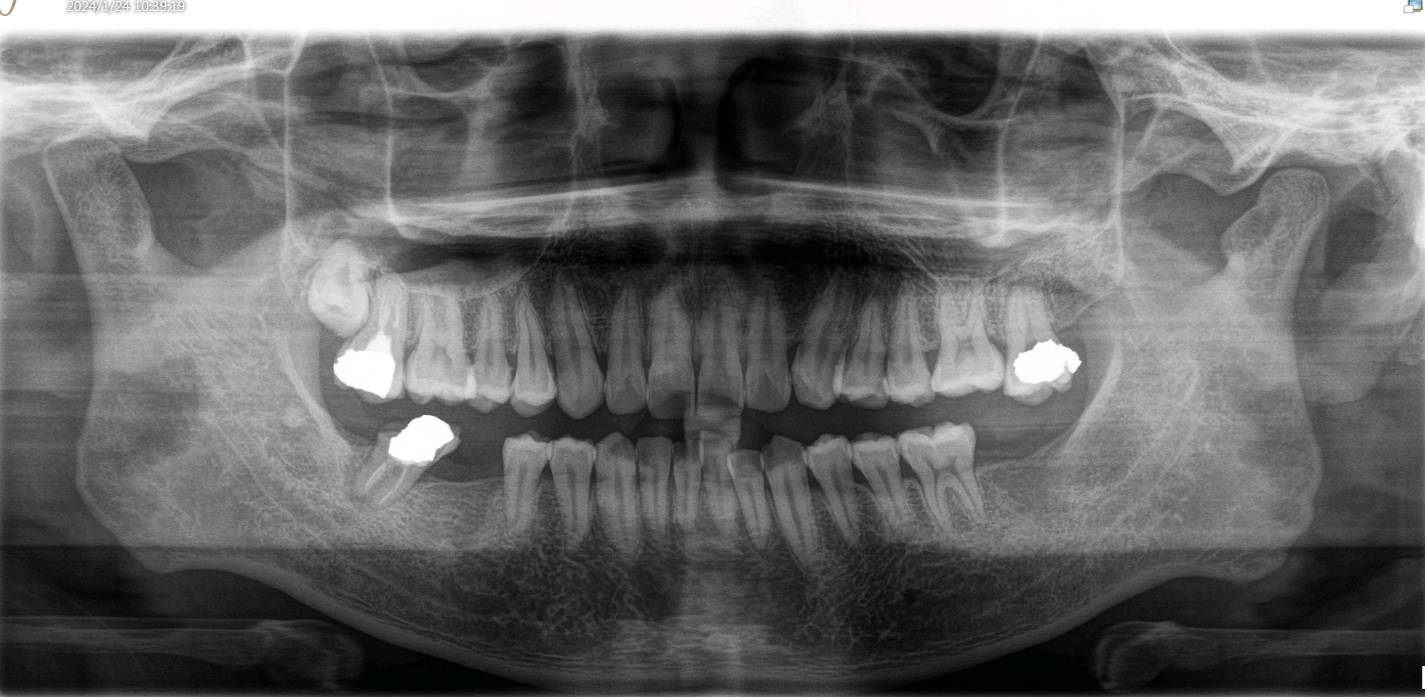

患者做完根管治疗后没有及时进行冠修复,吃东西的时候把原来做过根管治疗的牙齿咬裂了。检查可见:近中邻颌面牙劈裂,至龈下3~4mm,颌面大面积银汞充填物。牙体松动+,探(-),扣(+)。X线示根尖周呈低密度影像。向患者解释病情及治疗方案,患者选择拔除后以种植牙填补空缺。